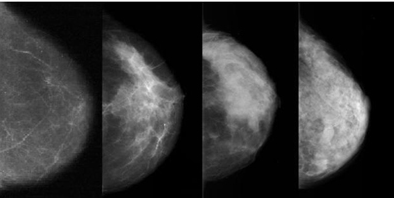

Far Left: Fatty Breast Tissue | Various Categories | Far Right: Extremely Dense